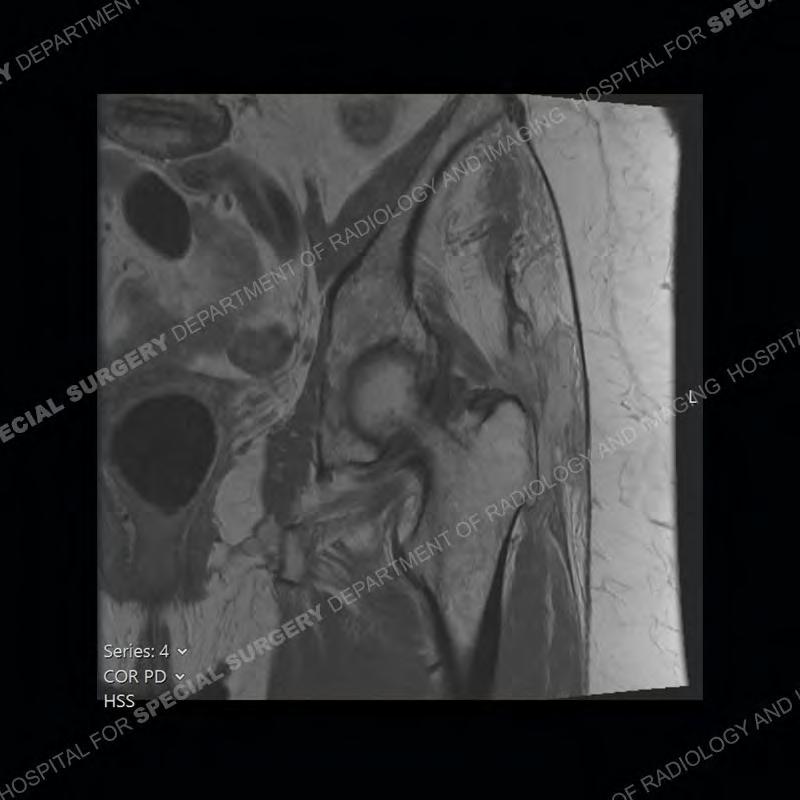

The radiograph is not particularly contributory in this case. The MRI demonstrates markedly abnormal architecture of the gluteus minimus and anterolateral band of the gluteus medius. Portions of the tendons are high signal, portions are highly attenuated, and portions are disrupted. A large, complex fluid collection is present in the adjacent soft tissue.

Diagnosis: Gluteal Tendinosis and Disruption with Complex Trochanteric Bursal Collection

Not as much of a diagnostic dilemma as many of the other cases shown but just a nice example of the pathology seen of the gluteal tendons and a cause of trochanteric pain. Although, frequently thought of in isolation, trochanteric bursitis or bursal thickening is much more commonly a reactive change to underlying pathology of the subjacent gluteal tendons. The gluteus medius is divided into a posterior band and an anterolateral band. Tendinosis and partial tearing very commonly will involve the gluteus minimus and especially the more posterior fibers and then propagate into the anterior lateral band of the gluteus medius. Involvement of the posterior band of the medius is much less common and engenders a marked degree of functional impairment.

The bursae about the greater trochanter can be a little bit confusing especially given the terminology. Trochanteric bursitis is implied to mean the subgluteus maximus bursa which is present deep to the maximus and just lateral/superficial to the trochanter. That is the bursa involved in this case. In this case the complexity of the bursa relates to the tendon tearing with inflammatory change and probably hemorrhage accounting for the complexity. Two other, less frequently involved bursa are also present. The subgluteus medius and subgluteus minimus bursa are found just deep to the named tendons. Although pathology does frequently follow the previously described pattern it is possible to have isolated pathology to either the medius or minimus.